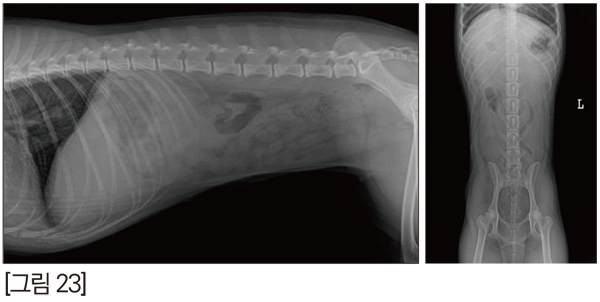

방사선 검사, 초음파 검사에서도 특이사항이 없었습니다. [그림 23]